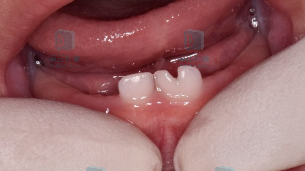

现在很多孩子换牙的时候会出现“双排牙”:新牙和旧牙排成两排,同时出现在口腔里。这种情况叫做乳牙滞留,俗称“双排牙””,简单来说就是旧的乳牙还没来得及脱落,新的恒牙就已经迫不及待的长出来了。

图片

出现双排牙,提前拔除滞留的乳牙有利于新牙尽早的排齐,同时也便于清洁尤其是上颌的双排牙,应尽早拔除滞留乳牙,避免造成前牙反颌。因此,如果孩子出现了双排牙情况,是时候去拜访一下牙医了。